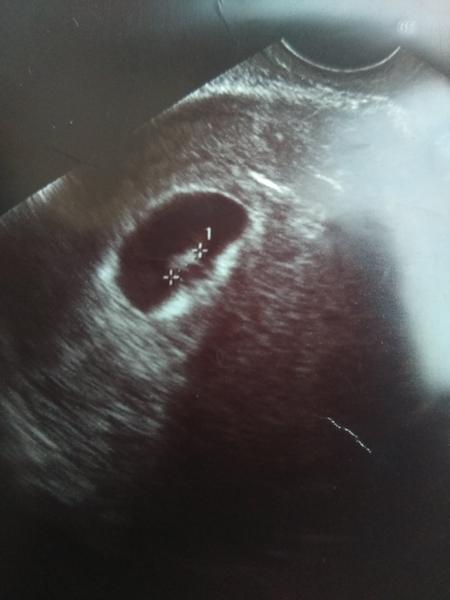

Ahoj holky přidávám se, já mám termín 6.9, už jsem byla u dr a viděla jsem srdíčko, další ko 5.2., jen máme prsa velký jak Andersonová (neříkám , manžel je spokojenej :D ) Ale pořád má bolesti zad a podřišku jako kdybych to měla dostat, máte to taky tak? :( mám dělohu plnou miomů, budu rodit asi na císaře dle dr tak mám strach :( u prvního těhu až mi narostl pupík tak jsem to cítila...držte se 🙂